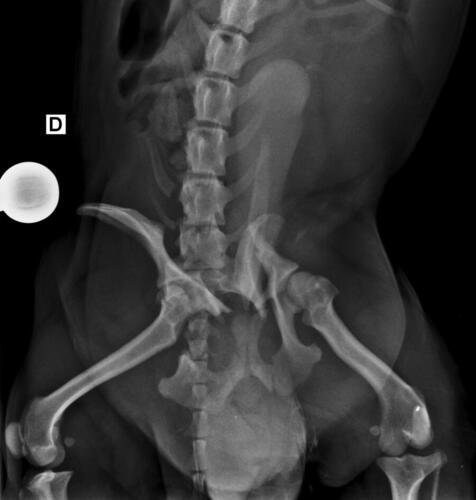

Olá, me chamo Jacqueline sou a mãe do chokito de 4 patas 🐶. No dia 07/02/2025 chokito foi atropelado em frente a minha casa, onde resultou no quadril dele quebrado e a patinha direita traseira quebrada tbm (a tíbia). Quem atropelou ele não parou pra prestar socorro a ele, e mto menos quis saber oque havia acontecido. Chokito foi atropelado na frente dos meus filhos, duas crianças um autista de 5 anos e uma criança de 3 anos, onde o acidente poderia ter acontecido com um deles, mas graças a Deus, Deus livrou eles, mas infelizmente o chokito não. Desde o dia 07 o chokito sofre de fortes dores constantes, onde ele não consegue se movimentar, para se alimentar ele precisa de ajuda, pra beber água, está com dificuldade em evacuar por conta das fortes dores que ele vem sentindo. Preciso de ajuda pra dar uma qualidade de vida pro chokito voltar a andar e parar de sentir dores constantes. A cirurgia ficou em torno de R$5,500 reais, um valor ao qual eu não consigo pagar, tudo tem sido mto caro, tenho gastado com remédios, Raio x, veterinário, já a cirurgia está mto a cima do que eu poderia pagar pra ajudar ele. Chokito é um cachorro que já foi abandonado e maltratado, pegamos amor e cuidamos dele, meus filhos sofrem por não poder brincar com o cachorro deles e ver o cachorro sempre gritando de dor é uma tristeza para todos nós. Por isso preciso de ajuda pra custear essa cirurgia que ele tanto precisa. Por favor quem puder me ajudar de alguma forma pra que ele volte a andar e parar de sofrer. Estou com meu coração dilacerado vendo ele sofrer sem poder fazer mais do que eu já estou fazendo que é cuidar dele. Cada dia que passa é mais tempo que ele passa sofrendo e agravando a situação que ele se encontra.